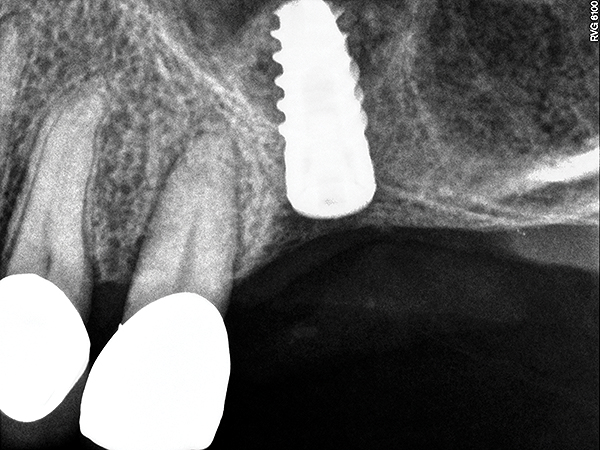

This patient was a 73-year-old man with only about 3.5 mm of native bone in the No. 3 site (Figure 20). The composite graft used here was a 50:50 mixture of DFDBA and deproteinized bovine bone mineral (Osteohealth, www.osteohealth.com) with approximately 40% calcium sulfate added. The implant was the same type and length as in Case 1 above. Figure 21 shows the area on the day of placement. In the CBCT scan on the day of placement (Figure 22), the native bone and bone graft were clearly discernable. However, the postoperative radiograph taken at 6.5 months (Figure 23) showed no marginal bone loss and a significantly denser appearance than when the graft was place. The membrane was raised about 7 mm to 8 mm. The final radiograph was taken after extraction of tooth No. 2 and after extraction of tooth No. 4 and immediate implant placement.

Fig 21. Day of sinus augmentation and implant placement in the No. 3 position. The sinus membrane has been raised about 7 mm to 8 mm.

Figure 21

Fig 22. CBCT scan (Kodak 9000D) of No. 3 area, day of placement. Appearance of native bone and bone graft is clearly discernible.

Figure 22

Fig 23. 6.5-month postoperative radiograph. Teeth Nos. 2 and 4 have been extracted and an immediate implant had been placed in the No. 4 position.

Figure 23